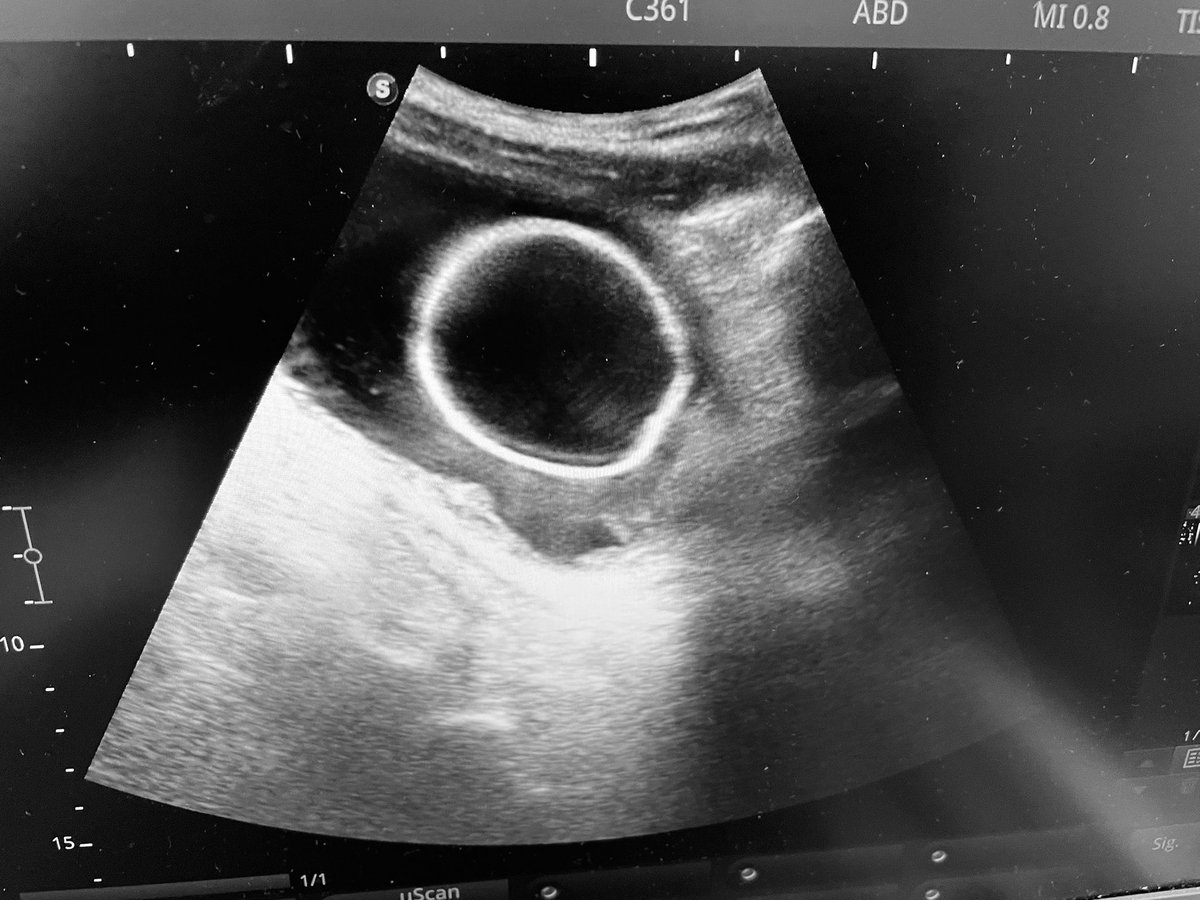

Think you need a CTU to detect duplex system? Not always! Careful US can alert you early and prevent wrong Ureteric catheter insertion — before PCNL, for example. #UroTips @Endo_Sec_Eua @Endo_Society @endouroacademy

Careful US can alert you early and prevent wrong Ureteric catheter insertion — before PCNL, for example. #UroTips @Endo_Sec_Eua @Endo_Society @endouroacademy